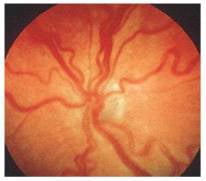

Página 323 - 9.3. Evolución de la ROP